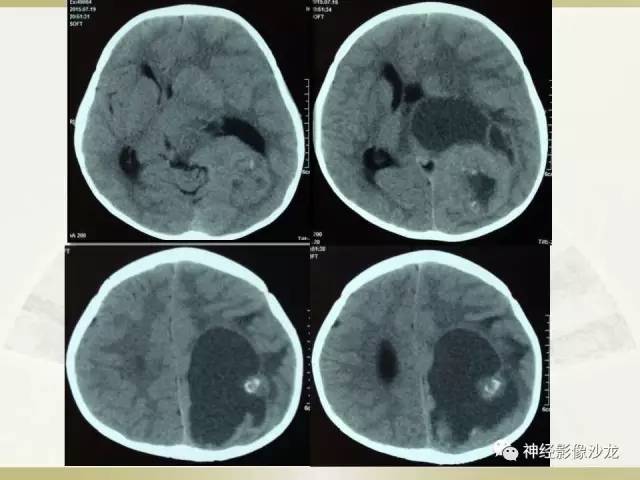

【病例】幕上脑实质内室管膜瘤1例CT及MR影像讨论

囊实性占位,有钙化,实性成分明显强化

周老师说过两大特点,钙化,囊变,白老师说DWI高

其内有钙化,DWI高信号

CT是钙化